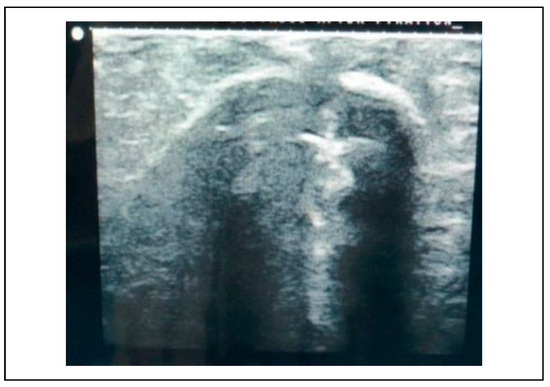

Ultrasonographic examinations were done before reduction, after reduction and after fixation at the frontozygomatic region, infraorbital rim and zygomatic buttress (refer Figure 3, Figure 4, Figure 5, Figure 6, Figure 7, Figure 8 and Figure 11, Figure 12 and Figure 13). The observations were entered on a Microsoft Excel (Microsoft Office Excel 2007 MSO12.04518.1014) spreadsheet with columns and rows (Table 1 and Table 2).

Figure 5.

Preoperative USG—zygomatic buttress.

The subjects of the study group underwent an ultrasonographic examination before reduction at the frontozygomatic region, infraorbital rim and zygomatic buttress to assess the discontinuity of the bony fractured margins which were surface marked using a dermi marker at the respective points (Figure 3, Figure 4, Figure 5). These points served as landmarks to assess the reduction of the fracture site post reduction and fixation.